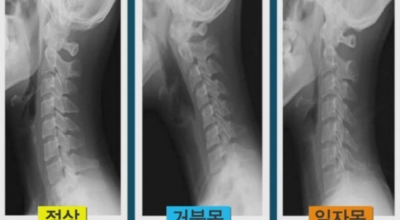

목디스크가 생기는 가장 큰 원인은 거북목과 일자목입니다. 신체의 가장 무거운 부분을 지지하는 경추는 옆에서 보았을 때 자연스러운 C자 모양을 보존시켜야 해요. 그러나 이 자세를 올바르게 유지하지 않고 머리를 숙이면 목의 무게는 머리 무게의 5배가 될 수 있어요. 이 경우에 목디스크가 발생해요. 거북목, 일자목 등 구부정한 자세를 방치하게 되면 어깨와 목 근육에 계속하여 압박이나 무리를 줌으로 인해 조기 치료가 중요해요. 목디스크를 방치하게 된다면 어깨 근육, 팔목, 손가락의 저림증상부터 마비증상까지 나타날 수 있답니다.